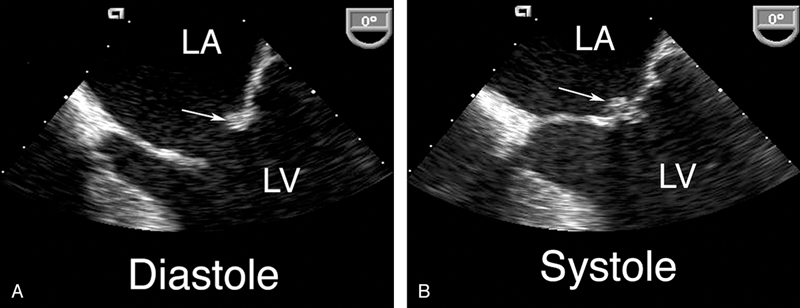

فحوصات تشخيصية لبعض امراض القلب والشرايين التاجية